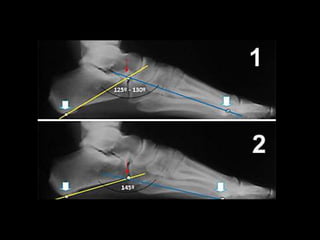

Evaluación Radiológica

• Pie plano: ángulo

calcaneo plantar <15º

• Pie normal : ángulo

entre 20º y 25º

• Pie cavo: ángulo >30º

ANGULO DE MOREAU

COSTA BARTANI

Define 2 arcos longitudinales

 Medial o interno

 Lateral o externo

• Interno:

Es el ángulo del polo inferior

del sesamoideo interno y el

punto más bajo de la cabeza

astragalina al punto más bajo

de la tuberosidad posterior

del calcáneo.

Su valor normal es 120-130°

PROYECCIONES LATERALES

ANGULO DE MOREAU COSTA

BARTANI

• Externo:

• Línea que une a la cabeza

del 5º. metatarsiano al

borde inferior de la

articulación calcaneo-

cuboidea al borde inferior

de la tuberosidad

posterior del calcáneo.

• Valor normal: 145°